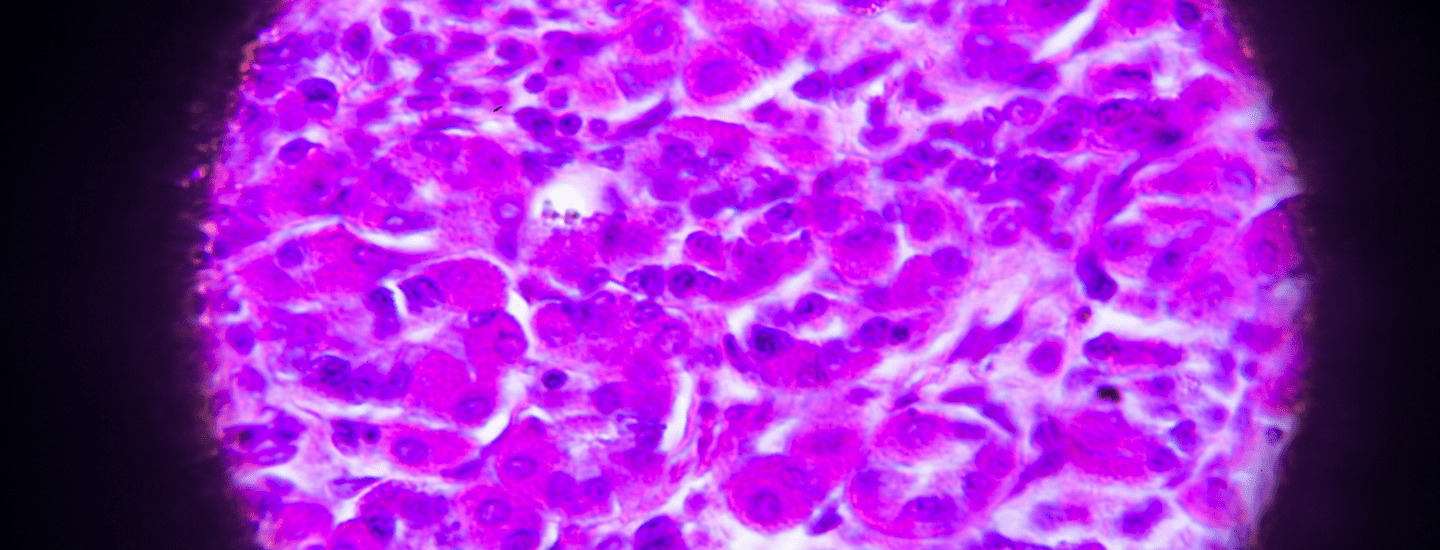

Around 90 to 95 per cent of Stomach Cancers develop in cells lining the mucosa – these are called adenocarcinomas, and they spread through the outer layers of the stomach. Other types include squamous cell carcinoma, lymphoma, stromal tumours, and carcinoid tumours, however these are rare.